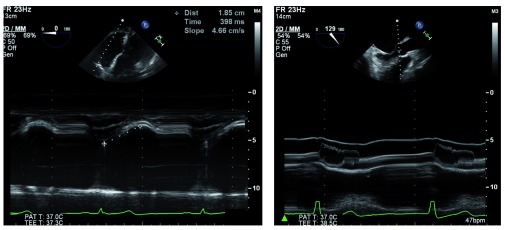

Figure 1. M-mode echocardiography is available on most modern transesophageal echocardiography probes.

It is clinically useful for diagnosing and characterizing many clinical conditions, such as right ventricular function, by measuring tricuspid annular plane systolic excursion (left) or assessing dynamic left ventricular outflow tract obstruction hallmarked by fluttering and premature closure of the aortic valve leaflets (right). 2D, two-dimensional; bpm, beats per minute; MM, M-mode; PAT T, patient temperature; TEE T, transesophageal echocardiography temperature.